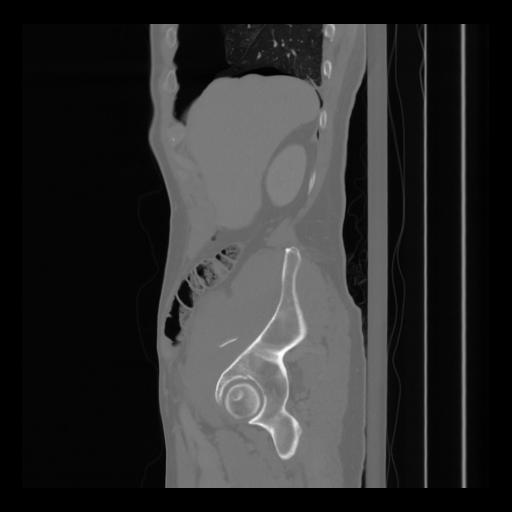

36 CUERPO,CE,Sagittal,3.000,CUERPO,Sagittal,